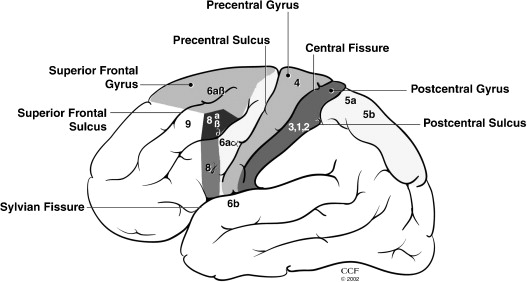

运动性语言中枢,又叫说话中枢,是语言中枢的一部分。运动性语言中枢位于大脑中的44及45区,紧靠中央前回下部,额下回后三分之一处,又称布若卡氏区。如果此区受损,会产生表达性失语症。能分析综合与语言有关肌肉性刺激。此处受损,病人与发音有关的肌肉虽未瘫痪,却丧失了说话的能力,临床上称运动性失语症(表达性失语症)。

雄辩皮层的功能映射是具有巨大科学和临床影响的目标应用。大约三分之一的癫痫患者癫痫发作对药物治疗有抗药性。在其中许多患者中,癫痫发作来自局灶性大脑区域,如果可以安全地切除该区域,就可以实现癫痫发作控制。当非侵入性测试无法可靠地识别癫痫发作区与正常神经功能所需的大脑区域不同时,临床医生可以选择在大脑深处(立体-EEG)或其表面(电皮质图或ECoG)手术植入电极。这些颅内电极可以植入一周或更长时间,以便可靠地定位癫痫发作的发作。这些电极还有助于识别雄辩的皮层,即与言语和语言以及感知、运动和其他重要大脑功能相关的区域。一种称为电皮质刺激映射(ESM)的技术通常用于映射这些区域。在ESM期间,在植入的电极对之间传递电流脉冲系统,以便在患者执行简单的语言或运动任务时暂时禁用一小块皮层。这种暂时性病变引起的行为变化表明,大脑的刺激区域是完成任务所必需的。但是这种测试程序对患者来说既费时又很不舒服,且出院后依旧有可能会癫痫发作。

ESM的局限性激发了一种互补的映射技术,该技术基于对行为任务期间ECoG或立体EEG被动记录的功率谱(特别是在高频)中与任务相关的变化的估计。这种映射技术,以下简称ECoG功能映射,生成与任务相关的皮层激活地图,其中可能包括任务招募但对任务性能不重要的皮层。相比之下,ESM使用皮层功能的暂时电生理破坏来模拟组织切除的急性行为影响,并被认为特定于对任务表现至关重要的区域。尽管如此,一些临床研究表明,ECoG功能映射和ESM之间存在良好的对应关系。此外,几项研究表明,ECoG功能映射可用于预测切除后的神经损伤,在某些情况下,它预测了ESM没有预测的损伤。由于这些原因,一些癫痫手术中心已经开始使用ECoG功能映射作为ESM的补充,有时提供皮层功能的初步地图,以指导ESM的使用。然而,由于缺乏技术资源,特别是可用于临床脑电图监测系统的软件,大多数癫痫中心尚未采用ECoG功能映射。近年来开发了几个ECoG功能映射包。例如,SIGFRIED在校准块中获得了神经活动的大量基线分布,然后通过平均行为在时间块中引发的神经活动来快速积累皮层激活的估计值。一种名为cortiQ的商业产品能够执行这种基于块的映射范式,这使得训练有素的临床专业人员能够进行被动ECoG映射。(SIGFRIED和cortiQ都是使用BCI2000框架构建的)